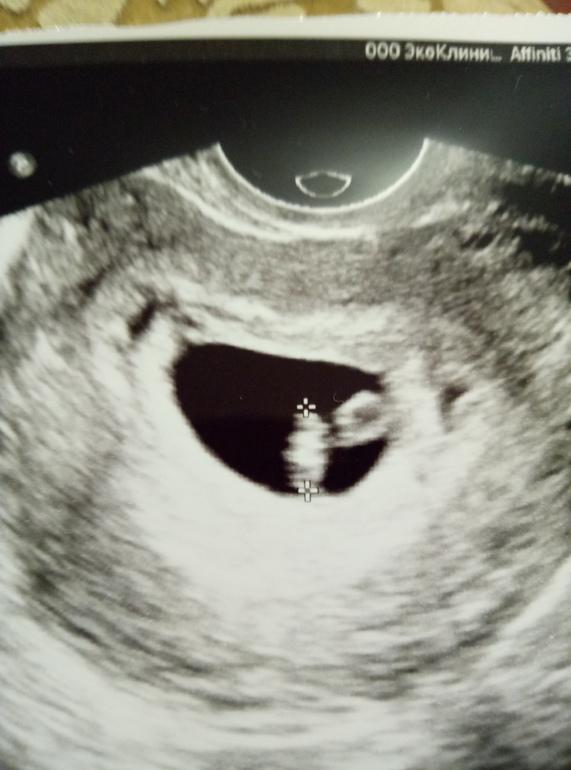

Узи 30дпп!6н 5дн

Сегодня повторили узи. Пя 18мм, эмбриончик 8мм.

Сб+